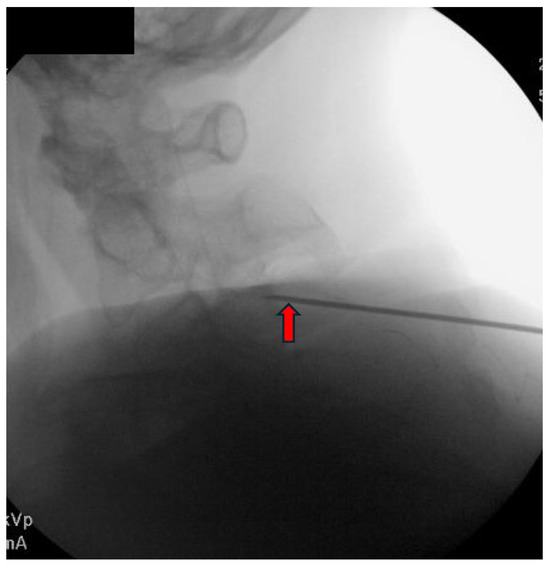

3.3. Procedure Description